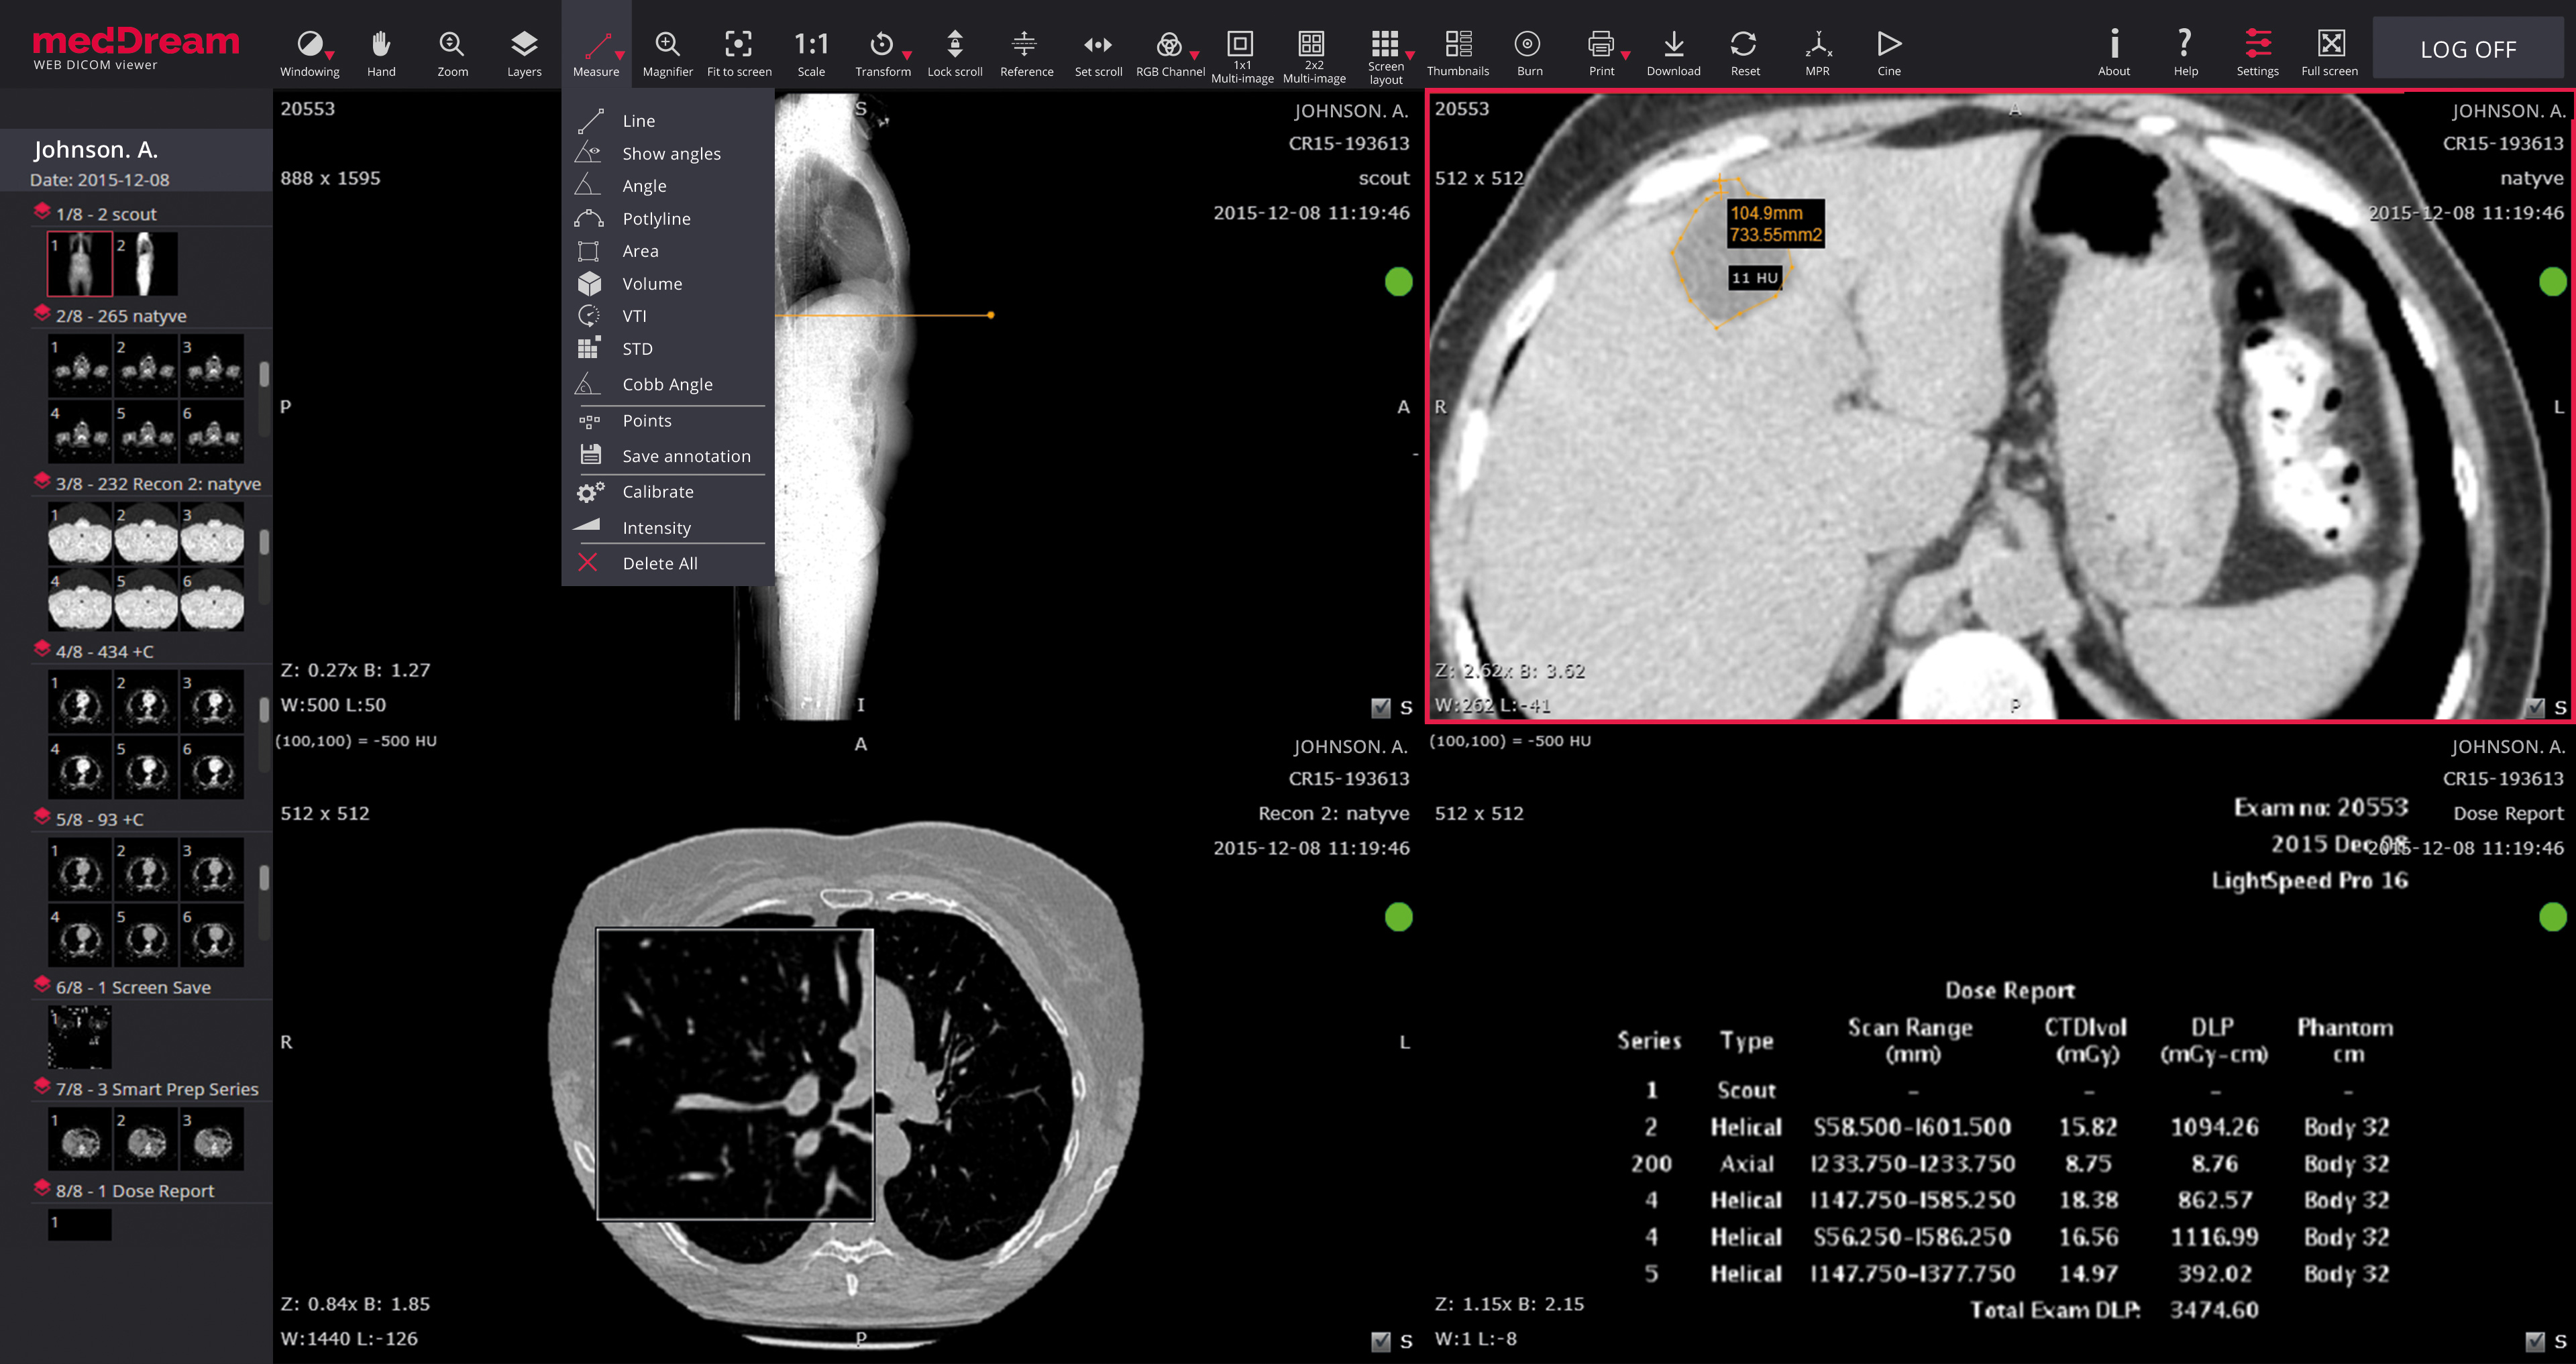

Лазерная камера для печати медицинских изображений на пленке стандарт dicom